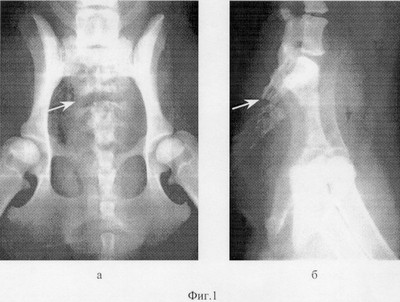

Фиг.1 – рентгенограмма таза животного до лечения: а – прямая, б – боковая проекции;

Собака, возраст 2 года, самка, диагноз: закрытый изолированный поперечный перелом крестца на уровне второго сегмента (фиг.1).